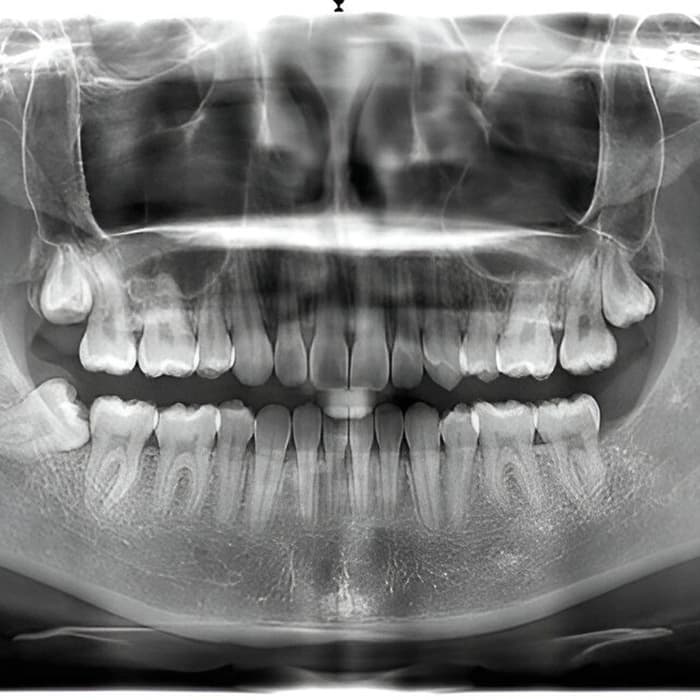

عکس OPG یا پانورامیک یک نوع رادیوگرافی دندانپزشکی است که نمایی گسترده و یکجای از هر دو فک، مفصلهای گیجگاهی–فکی (TMJ)، سینوسهای فکی و وضعیت کلی دندانها ارائه میدهد. این تصویر برای بررسی دندانهای نهفته (مثل دندان عقل)، ارزیابی تراکم و ارتفاع استخوان، تشخیص ضایعات فکی، برنامهریزی درمانهای ارتودنسی و ایمپلنت بسیار کاربردی است. با یک تصویر، دیدی کلی از دهان و فکها به دندانپزشک میدهد تا مسیر تشخیص و درمان دقیقتر شود.

در OPG بیمار میایستد یا مینشیند، سر با نگهدارنده مخصوص ثابت میشود و دستگاه بهآرامی دورتادور صورت میچرخد و تصویری پانورامیک ثبت میکند. کل فرایند کوتاه، بدون تماس دردناک و با دوز پرتوی پایین و ایمن انجام میشود. در صورت بارداری یا احتمال آن، حتماً پیش از تصویربرداری به پذیرش اطلاع دهید.

بررسی دندانهای نهفته و رویش نابجا (خصوصاً دندان عقل)

ارزیابی کلی وضعیت دندانها پیش از ارتودنسی

برنامهریزی کاشت ایمپلنت و سنجش ارتفاع/پهنای استخوان

بررسی ضایعات، کیستها و تومورهای فکی، تروما و شکستگیها

پایش بیماریهای گسترده لثه و استخوان یا عوارض سینوسی مرتبط

OPG تصویری سریع، ایمن و فراگیر از دهان و فکها ارائه میدهد و ابزار کلیدی برای تشخیص و برنامهریزی درمانهای ارتودنسی، جراحی، ایمپلنت و مدیریت دندانهای نهفته است. اگر دندانپزشک شما OPG توصیه کرده، با یک عکس بهروز و باکیفیت میتوان از تکرار تصویربرداریهای متعدد جلوگیری کرد و روند درمان را دقیقتر و سریعتر پیش برد. برای اطلاع از هزینه دقیق در سال ۱۴۰۴، با مرکز تصویربرداری یا کلینیک خود تماس بگیرید.